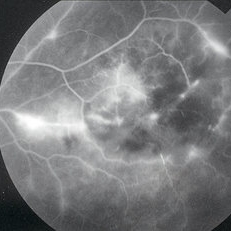

Mid-peripheral retinal vascular changes on late-phase fluorescein angiography of a 23-year-old Vietnamese female with Eales disease.

Imaging device: Topcon VT-50

Condition/keywords: Eales disease, FA late phase, FA late phase leakage, fluorescein angiogram (FA), retinal vasculitis